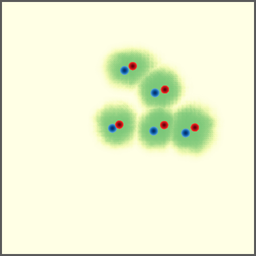

Shift-Invariant Tracking. The POINT network benefits from the shift invariant property of the convolution operation, which makes it less sensitive to the in-plane offset of the DRRs. Figure 8 shows some tracking results from the POINT network. Here the odd rows show the (a) X-ray and (b-d) DRR images. The heatmap below each DRR shows the tracking result between this DRR and the leftmost X-ray image. The red and the blue marks on the X-ray and DRR images denote the POIs. The red and the blue marks on the heatmaps are the ground truth POIs and the tracked POIs, respectively. The green blobs are the heatmap responses and they are used to generate the tracked POIs (blue) according to Equation (7). The numbers under each DRR denote the mPD scores before and after the tracking. As we can observe that the tracking results are consistently good, no matter how much initial offset there is between the DRR and the X-ray image. This shows that our POINT network indeed benefits from the POI convolution layer and provide more consistent outputs regardless of the in-plane offsets.

Refer to caption

(a)

(b) 13.6 \rightarrow 7.3

(c) 22.9 \rightarrow 9.0

(d) 37.1 \rightarrow 7.8

(e)

(f) 19.5 \rightarrow 8.7

(g) 26.0 \rightarrow 9.5

(h) 41.1 \rightarrow 11.4

(b)

(c)

(d)

Figure 8: POI tracking results. (a) X-ray image. (b-d) DRR images with different in-plane offsets. The heatmaps of the tracking results are all aligned with the X-ray images and appear similar, showing the shift-invariant property.